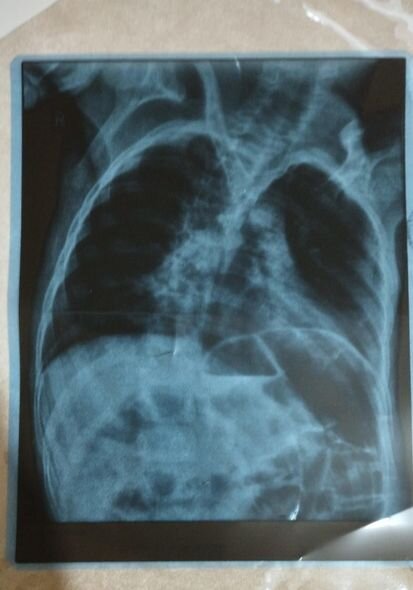

O bildirib ki, övladı serebral iflicdən əziyyət çəkir.

Nərminə Əzizova bildirib ki, Ömərə hazırda sətəlcəm diaqnozu qoyulduğunu deyib.

"Öməri soyuq havalarda qətiyyən çölə çıxarmırıq. Qış ərzində ancaq evdə olur. Evin istisinə o qədər öyrəşir ki, çox az müddətə çölə çıxanda xəstələnir. Həkimlər ona sətəlcəm diaqnozu qoyub. Mənim Ömərlə birgə 3 övladım var, uşaqların üçü də qızılca olub. İnanın həm uşaqların qızılcası, həm Ömərin xəstəliyi bizi əldən salıb - heç nəyi çatdıra bilmirik. Ömərin müalicəsi üçün hazırda 200 manata ehtiyacımız var. Yardımsevər şəxslərdən bizə dəstək olmalarını xahiş edirəm".